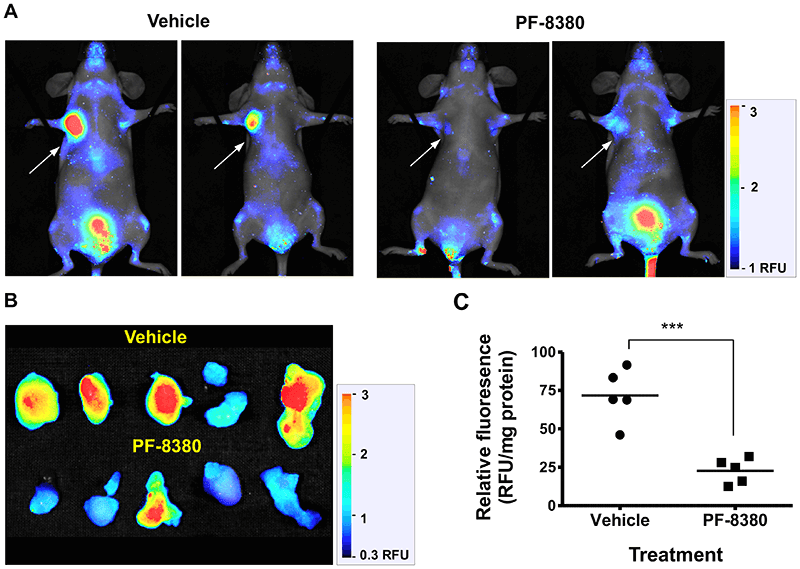

- Ex vivo biodistribution analysis examines excised animal tissues (tumors, organs) for relative accumulation of your therapeutic. Macroscopic analysis of tissue sections and whole organ imaging allow a quick screening overview, while microscopic analysis confirms tissue localization of your dye-labeled therapeutic.

Deep light penetration and minimal autofluorescence from animal tissues make NIR detection ideal for tracking biodistribution and clearance with high sensitivity. Low background yields excellent signal-to-noise ratios for monitoring your dye-labeled therapeutic in vivo and ex vivo.

The Pearl Trilogy Small Animal Imaging System can perform rapid time-lapse in vivo imaging without the need to manually adjust camera settings between scans. For ex vivo analysis, the Organ Tray Base and disposable organ trays provide a non-heated, flat surface for imaging on the Pearl Trilogy system. IRDye Infrared Dyes IRDye 800CW and IRDye 680RD provide excellent performance for in vivo and ex vivo biodistribution and clearance imaging.